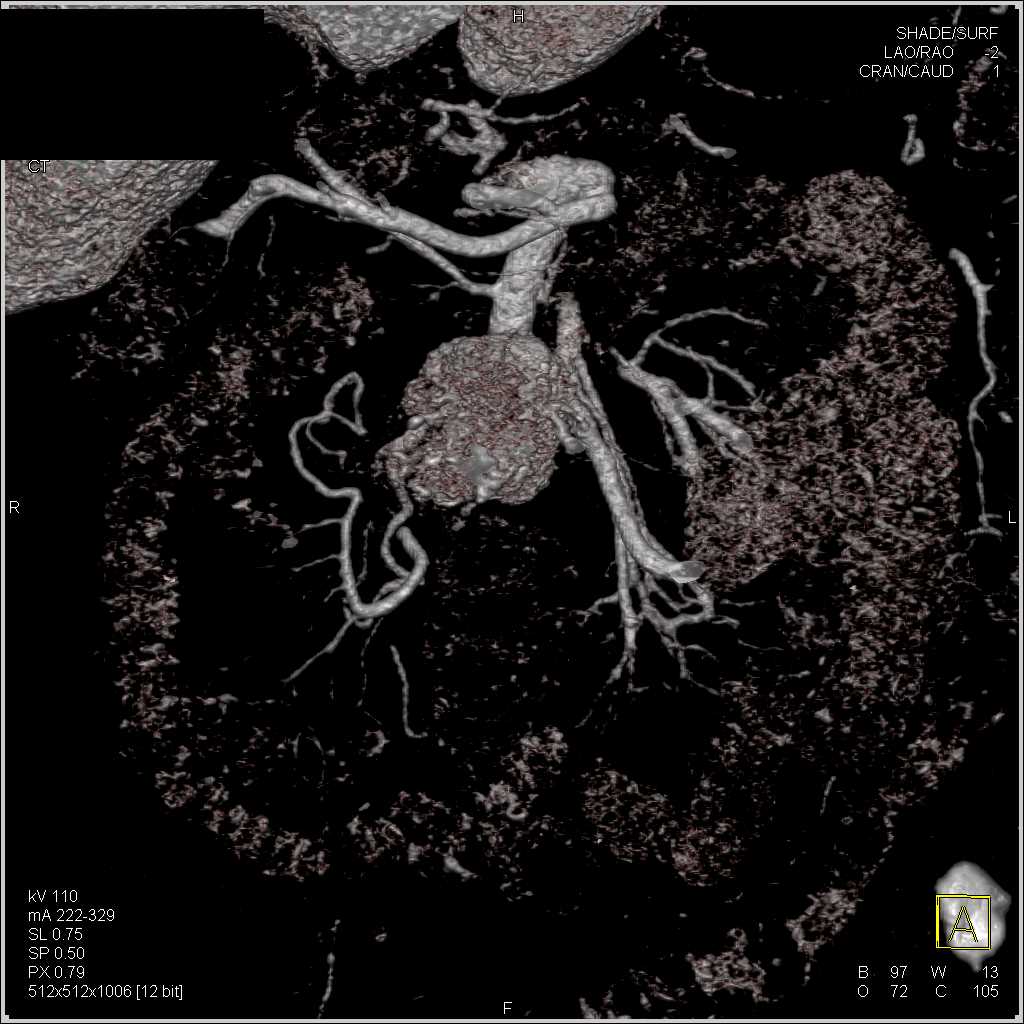

Carcinoid Tumor with Desmoplastic Reaction